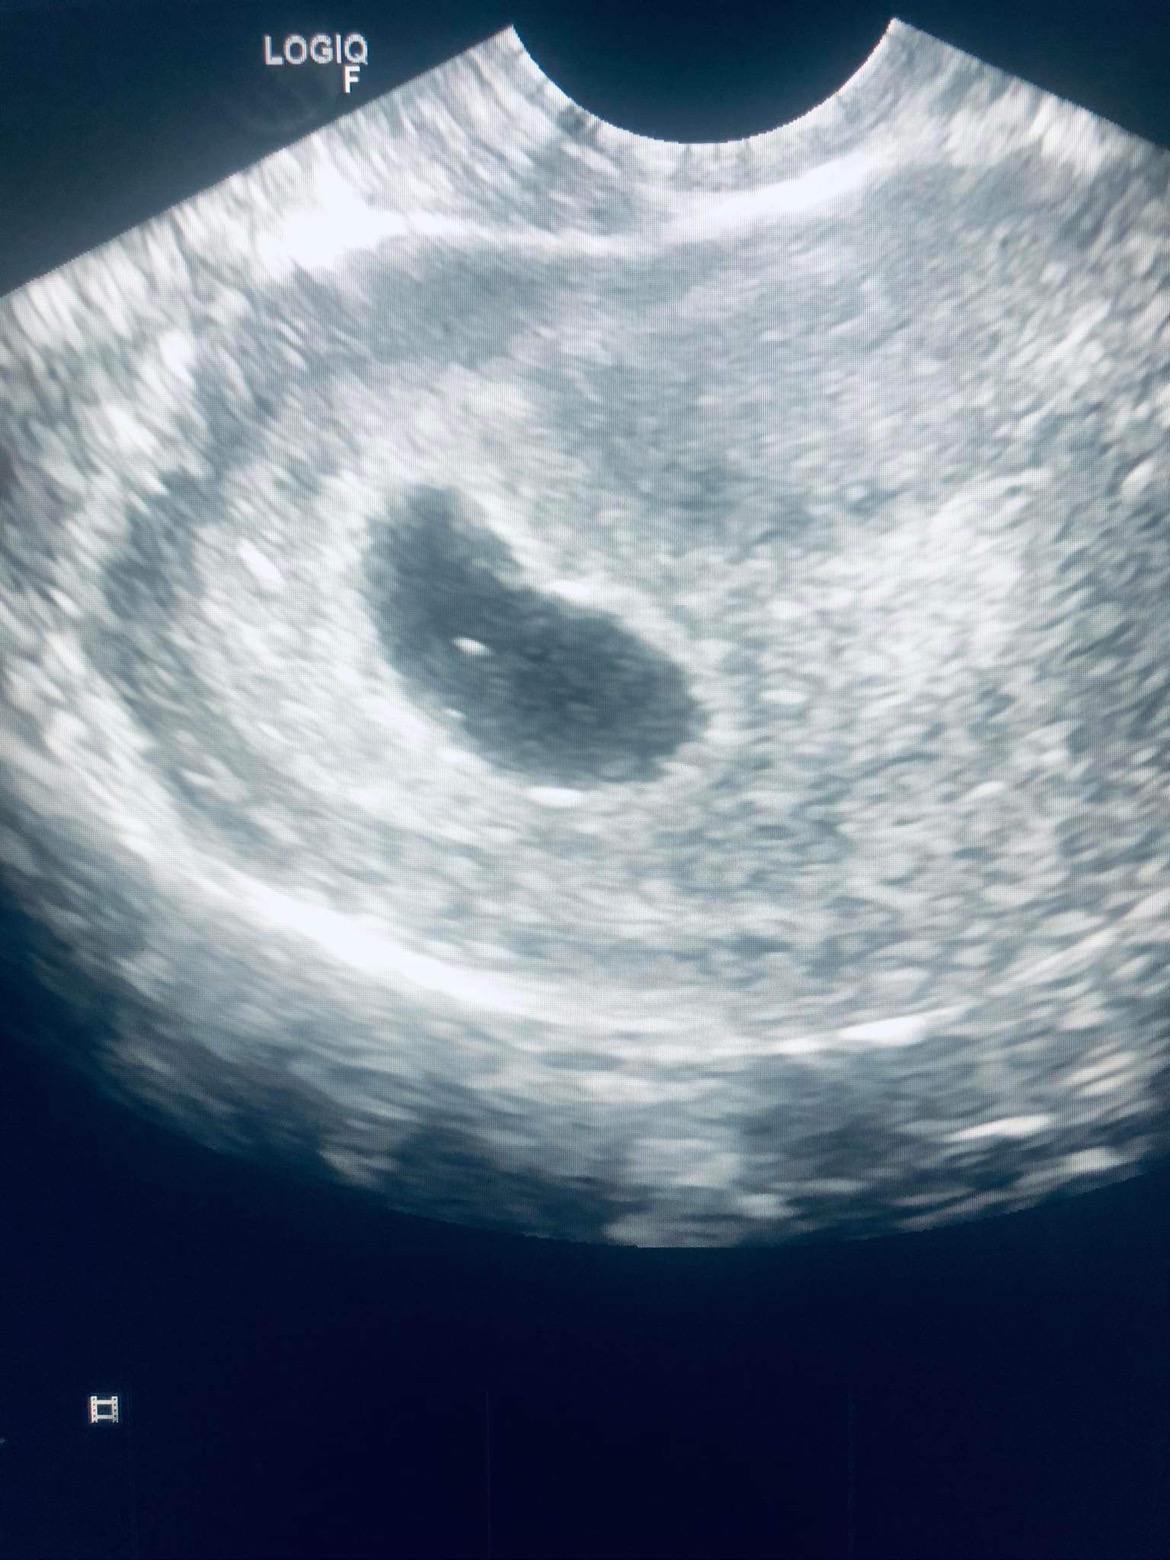

สอบถามหนีอยค่ะ จำวันประจำเดือนไม่ได้ แต่จำได้ว่ามีอะไรกับแฟนไปได้26วัน ไปหาหมอ แต่หมอไม่แจ้งอะไรเลย ไม่แจ้งว่ามีกี่สัปดา